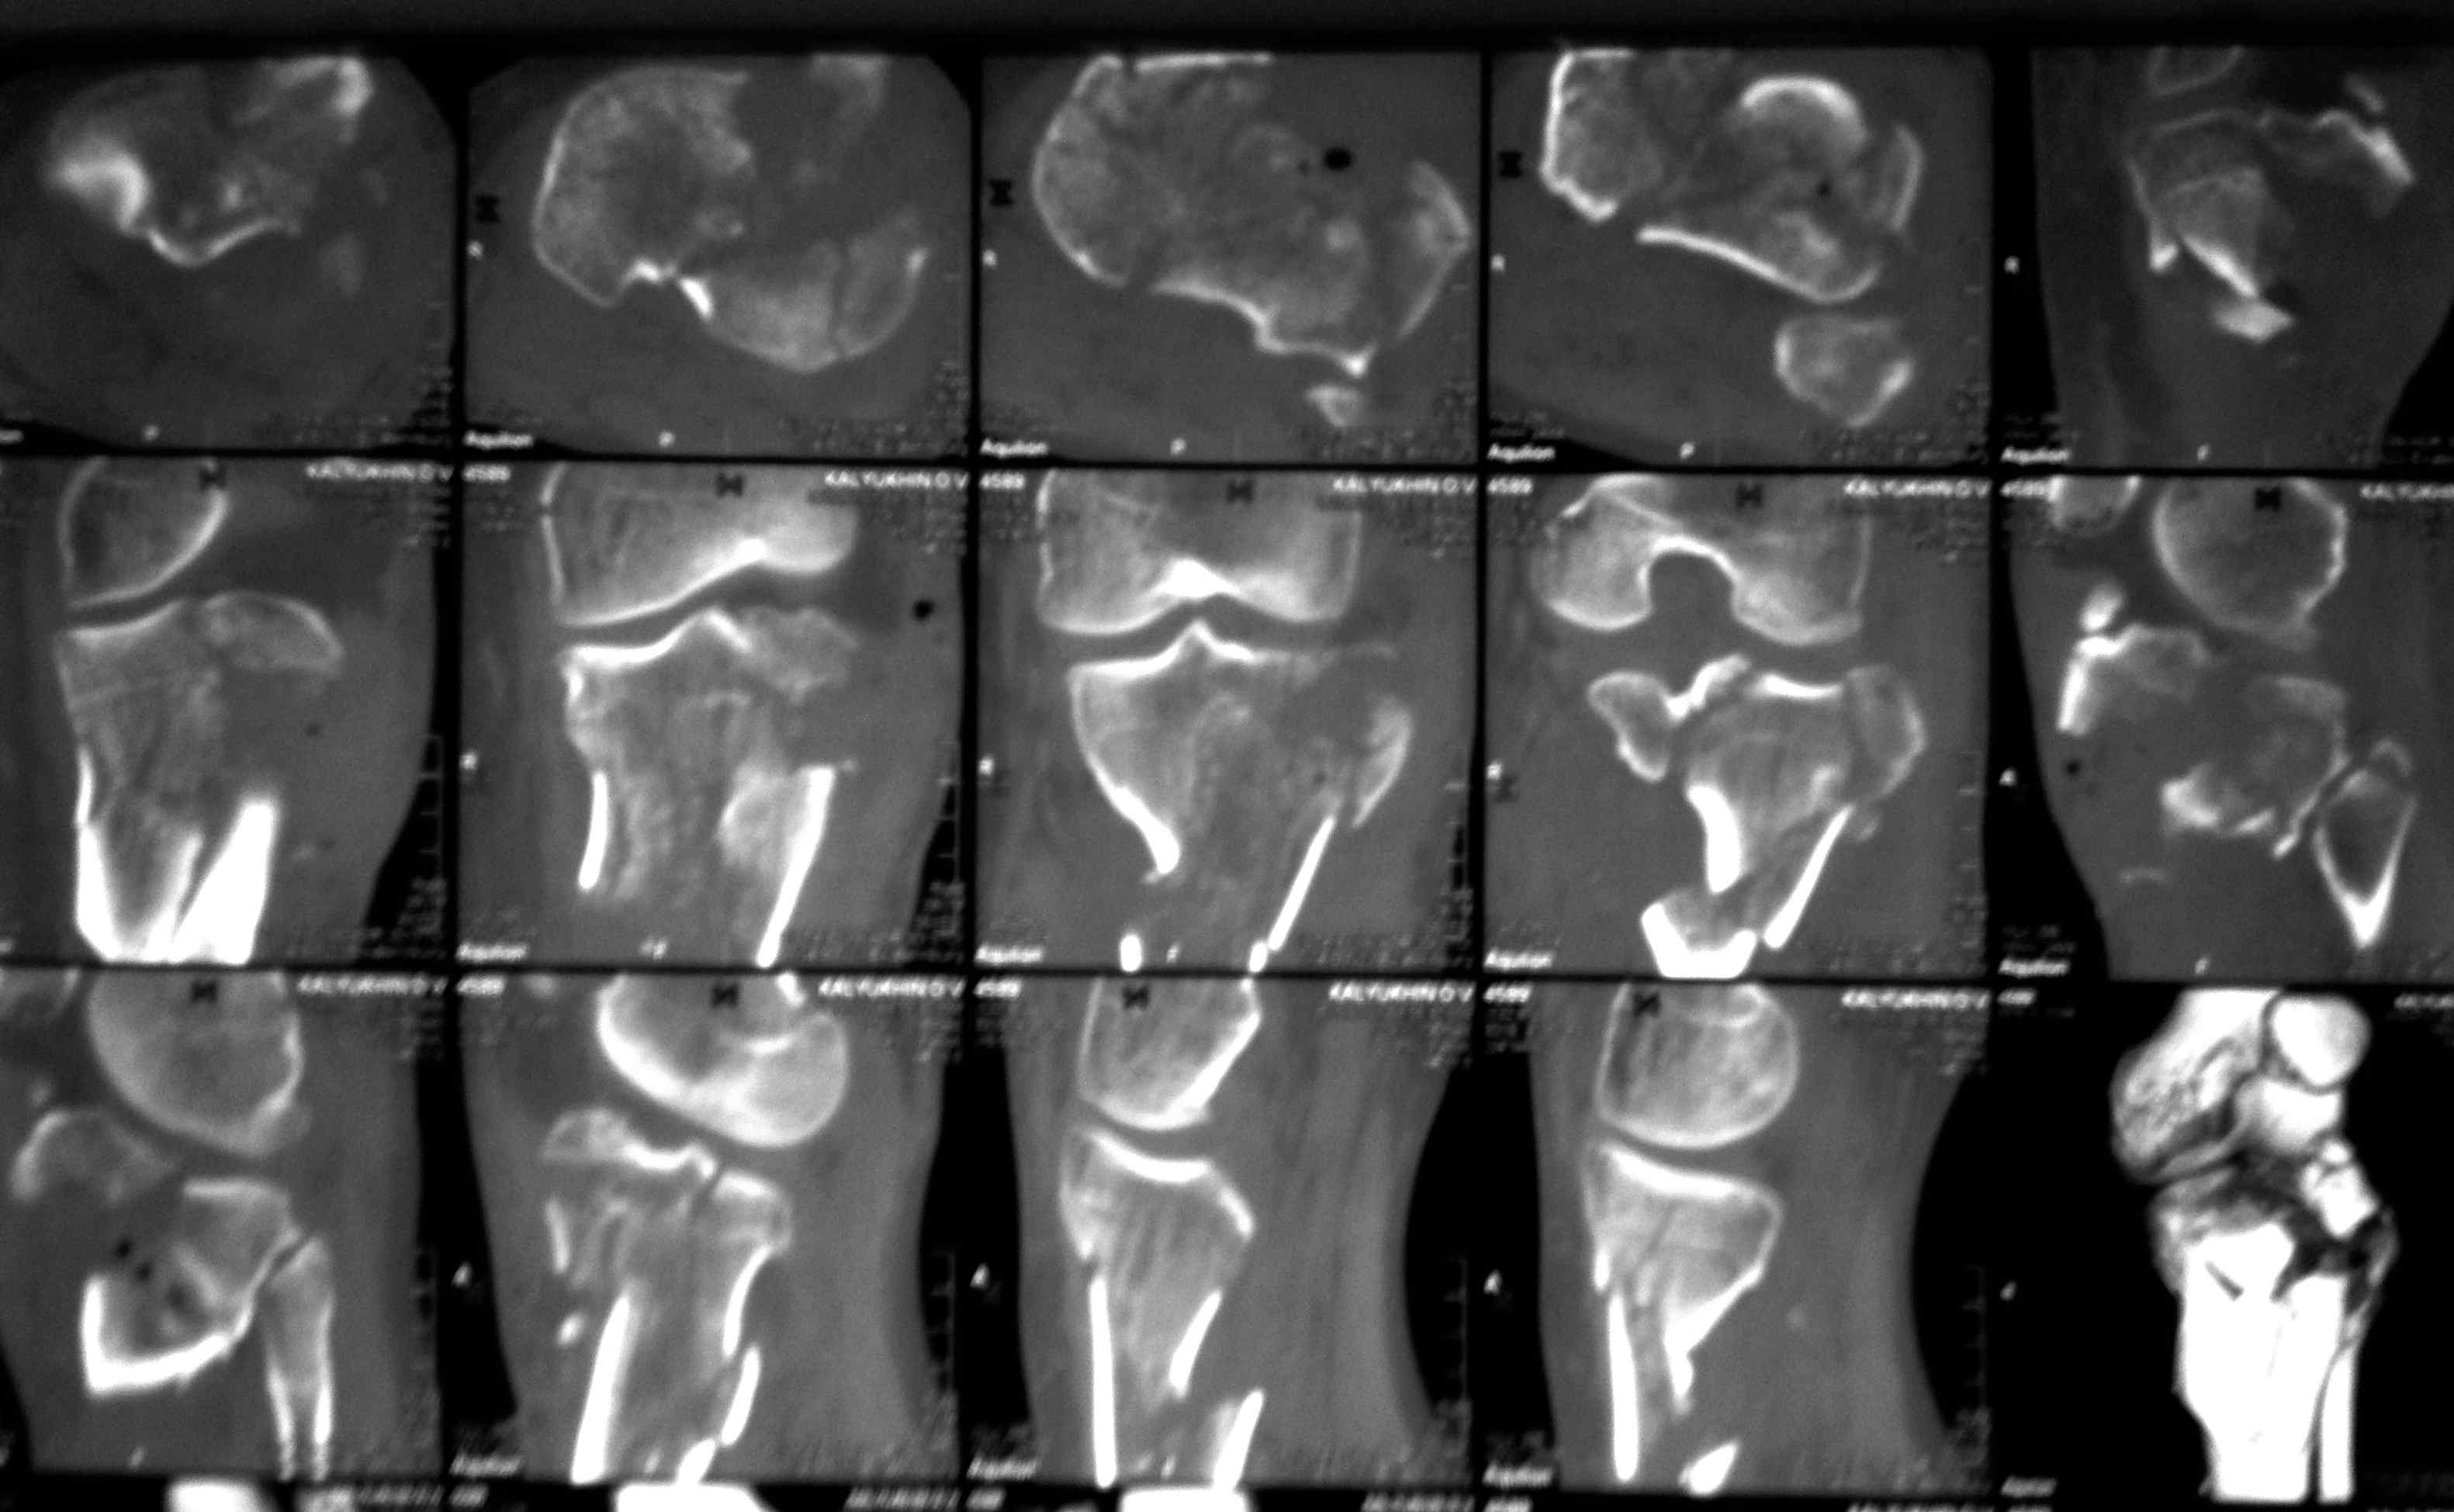

Серия КТ сканов в аппарате

Голень-41-С3.1 - полный внутрисуставной и метафизарный оскольчатый перелом с доминантным повреждением наружного мыщелка, с импрессией центральной части плато. Первичная тактика полный респект по АО и ОТА. на фоне лигаметотаксиса выполнено КТ, которое четко детализирует повреждение и определяет дальнейшую тактику.

Основная проблема не бугристость, а внутрисуставное повреждение латерального мыщелка с импрессией центральной части. С большей вероятностью, есть паракапсуллярное продольное повреждение наружного мениска.

Поэтому, после монолатерального АВФ, мы выполняем открытую реконструкцию. Медиальный мыщелок - 1, поскольку простой внутрисуставной перелом. Латеральный мыщелок -2 , с костной аутопластикой, из этого же доступа и бугристость. С большей вероятностью наружный мениск будет оторван паракапсуллярно, но это облегчит элевацию латерального плато. По окончанию операции его небходимо подшить.

Итак: изнутри 1\3 трубка или Т-обраная пластина, снаружи PTP LCP БУГРИСТОСТЬ - 2 мя винтами бикортикально